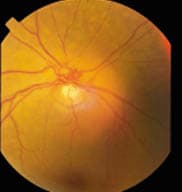

Optic disk photographs showing large c/d ratios

OS.

After dilation, I examined Sadie's optic nerves with a 78.00D lens. They looked classically glaucomatous. Sadie was a +4.00D hyperope and she had small optic nerve heads (ONH), yet her cup-to-disc ratio (c/d) was large and asymmetrical. I estimated her c/d ratio at .55 OD and .7/.7 OS (see photo at left). In addition, the cupping was deep and the lamina was visible in the base of the cup.